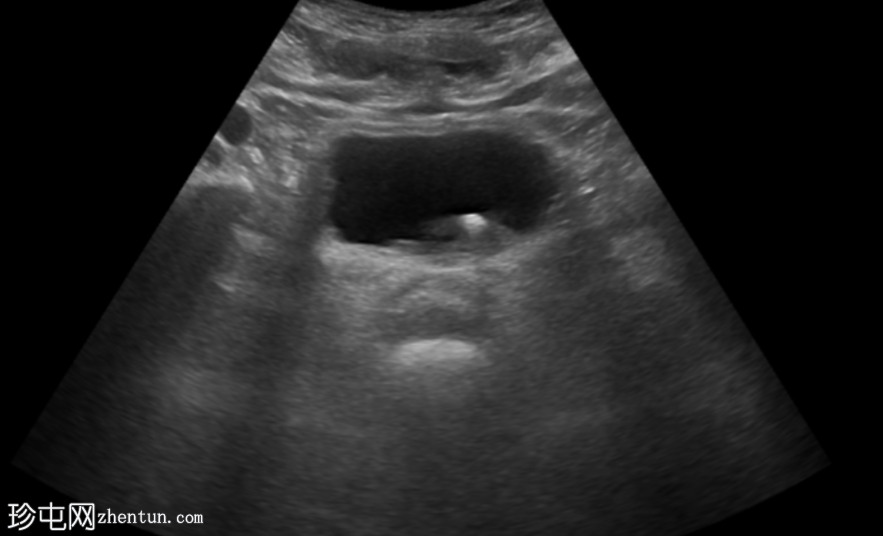

超声显示左侧轻度肾积水,由膀胱输尿管连接处一枚7毫米的远端输尿管结石阻塞所致,输尿管射流正常。

肾积水并非总是由输尿管结石引起。肾盂和肾盏扩张的程度与结石大小并不一定相关。

较小的结石有时可导致中度上游扩张,而较大的结石可能仅引起轻微的充盈感,这取决于患者的引流和水合状态。